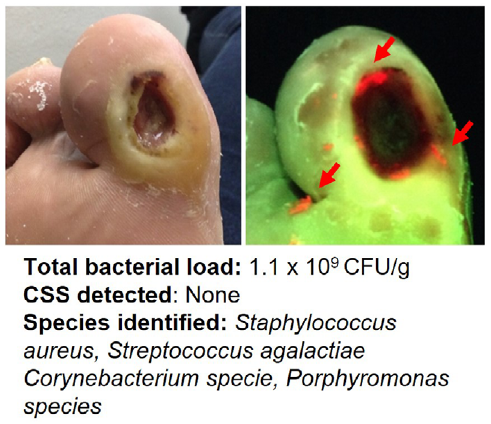

Point-of-care fluorescence imaging reveals extent of bacterial load in diabetic foot ulcers

Armstrong, DG et al. Int Wound J 2023